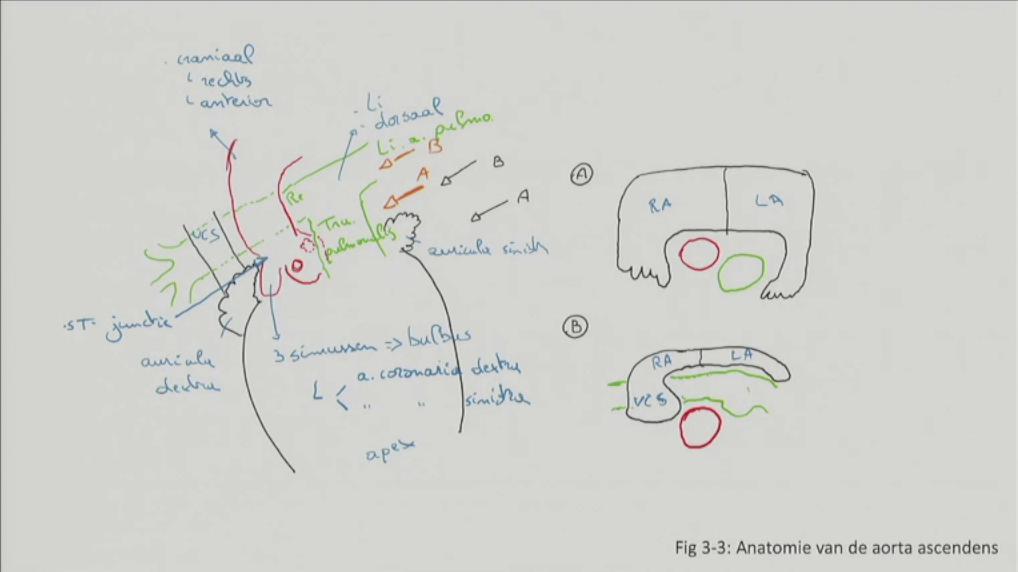

Fig 3.01: Schema grote en kleine bloedsomloop

atrium dextrum (RA) atrium sinistrum (LA) ventriculus dexter (RV) ventriculus sinister (LV)

arteries: weg van hart, onder hoge Druk venen: naar hart rood: zuurstofrijk bloed blauw: zuurstofarm bloed -

systeemcirculatie (120/80 mmHg)

pulmonaalcirculatie (25/10 mmHg, zelfde opdeling)